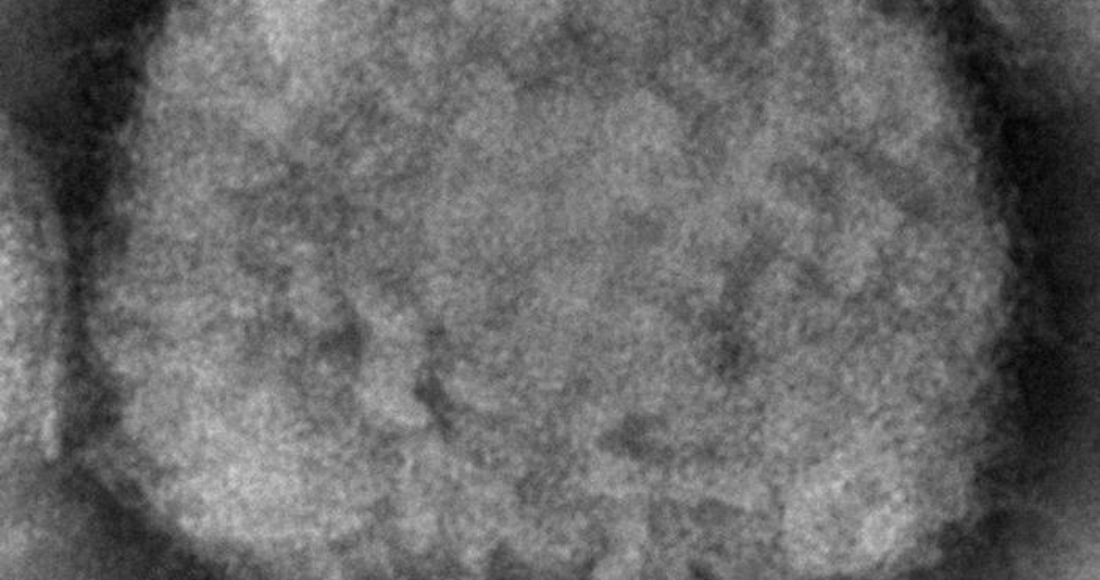

A diferencia de otros virus, la estructura de los virus de este grupo es muy compleja. Eso les permite usar diferentes mecanismos para infectar las células a las que invade, incluyendo la hemaglutinina utilizada por los virus de la gripe. Los simios y los humanos somos tan parecidos que un virus que afecte a los simios puede sin duda afectar a los humanos empleando los mismos mecanismos. Al fin y al cabo no somos más que una rama evolutiva desgajada del tronco común del que también salen nuestros primos, los simios. Y, además, la variolización utilizada por Edward Jenner para inmunizar a casi toda la humanidad se basa en este principio: la similitud entre el virus de la viruela vacuna y el humano.

Una particularidad interesante de estos virus es que se dispersan entre las células pasando directamente de una célula infectada a otra no infectada mediante puentes generados por el citoesqueleto. Es decir, manipulan la organización del citoesqueleto para generar puentes que permitan el paso de los virus de una célula a otra sin necesidad de salir al exterior. Mantenerse “escondidos” hace que el sistema inmunitario basado en anticuerpos no los pueda detectar con facilidad.